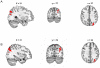

Damage to the parietal lobe can induce a condition known as spatial neglect, characterized by a lack of awareness of the personal and/or extrapersonal space opposite the damaged brain region. Spatial neglect is commonly assessed clinically using either the line bisection or the target cancellation task. However, it is unclear whether poor performance on each of these two tasks is associated with the same or different lesion locations. To date, methodological limitations and differences have prevented a definitive link between task performance and lesion location to be made. Here we report findings from a voxel-based lesion symptom mapping (VLSM) analysis of an unbiased selection of 44 patients with a recent unifocal stroke. Patients performed both the line bisection and target cancellation task. For each of the two tasks a continuous score was incorporated into the VLSM analysis. Both tasks correlated highly with each other (r = .76) and VLSM analyses indicated that the angular gyrus was the critical lesion site for both tasks. The results suggest that both tasks probe the same underlying cortical deficits and although the cancellation task was more sensitive than the line bisection task, both can be used in a clinical setting to test for spatial neglect.